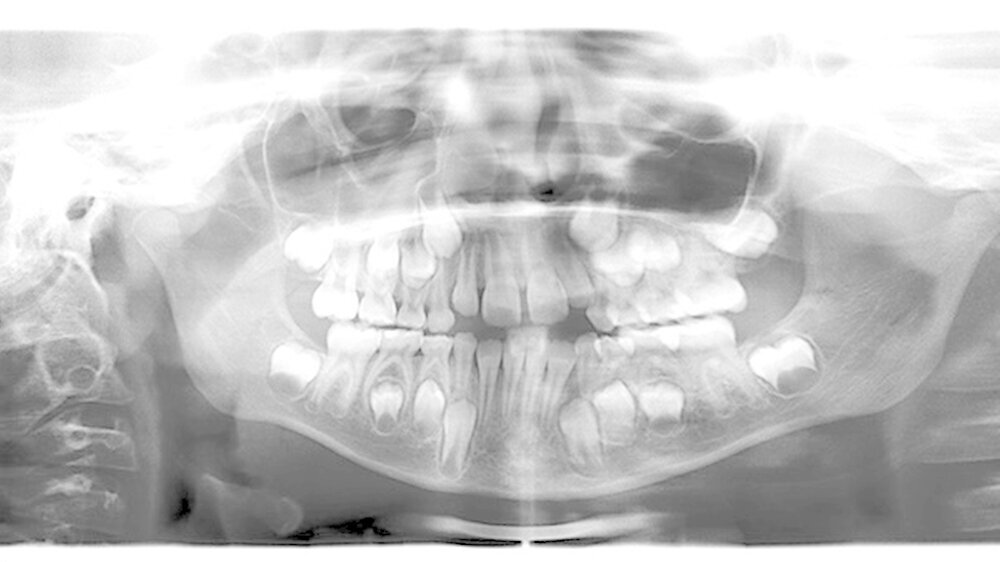

Die Erfolgsrate endodontischer Behandlungsmaßnahmen im Milchgebiss ist dann hoch, wenn die (Kontra-)Indikation korrekt gestellt wird. Als häufigstes Verfahren kommt die Caries-profunda-Therapie zum Einsatz, berichtet Prof. Roswitha Heinrich-Weltzien (Jena) und Prof. Jan Kühnisch (München) aktuell in der Zeitschrift "Oralprophylaxe & Kinderzahnheilkunde". Diese Therapie zielt auf die Vitalerhaltung der klinisch symptomlosen Pulpa ab.

Mit der selektiven Kariesexkavation stehe zudem eine schonenede Herangehensweise zur Verfügung, die vielen Herausforderungen in der Behandlung des kindlichen Patienten gerecht wird. Im Fall der Pulpabeteiligung sei die Pulpotomie insbesondere an Milchmolaren indiziert.

Die Pulpektomie und Wurzelkanalfüllung werde am häufigsten an Milchfrontzähnen bei Kindern mit frühkindlicher Karies praktiziert. Für die zeitige Sicherung des Therapieerfolgs nach einer endodontologischen Behandlung ist die Einbeziehung der Patienten in ein alters- und risikoadäquates Recall- und Präventionsprogramm eine unabdingbare Voraussetzung, betont die Autorin.